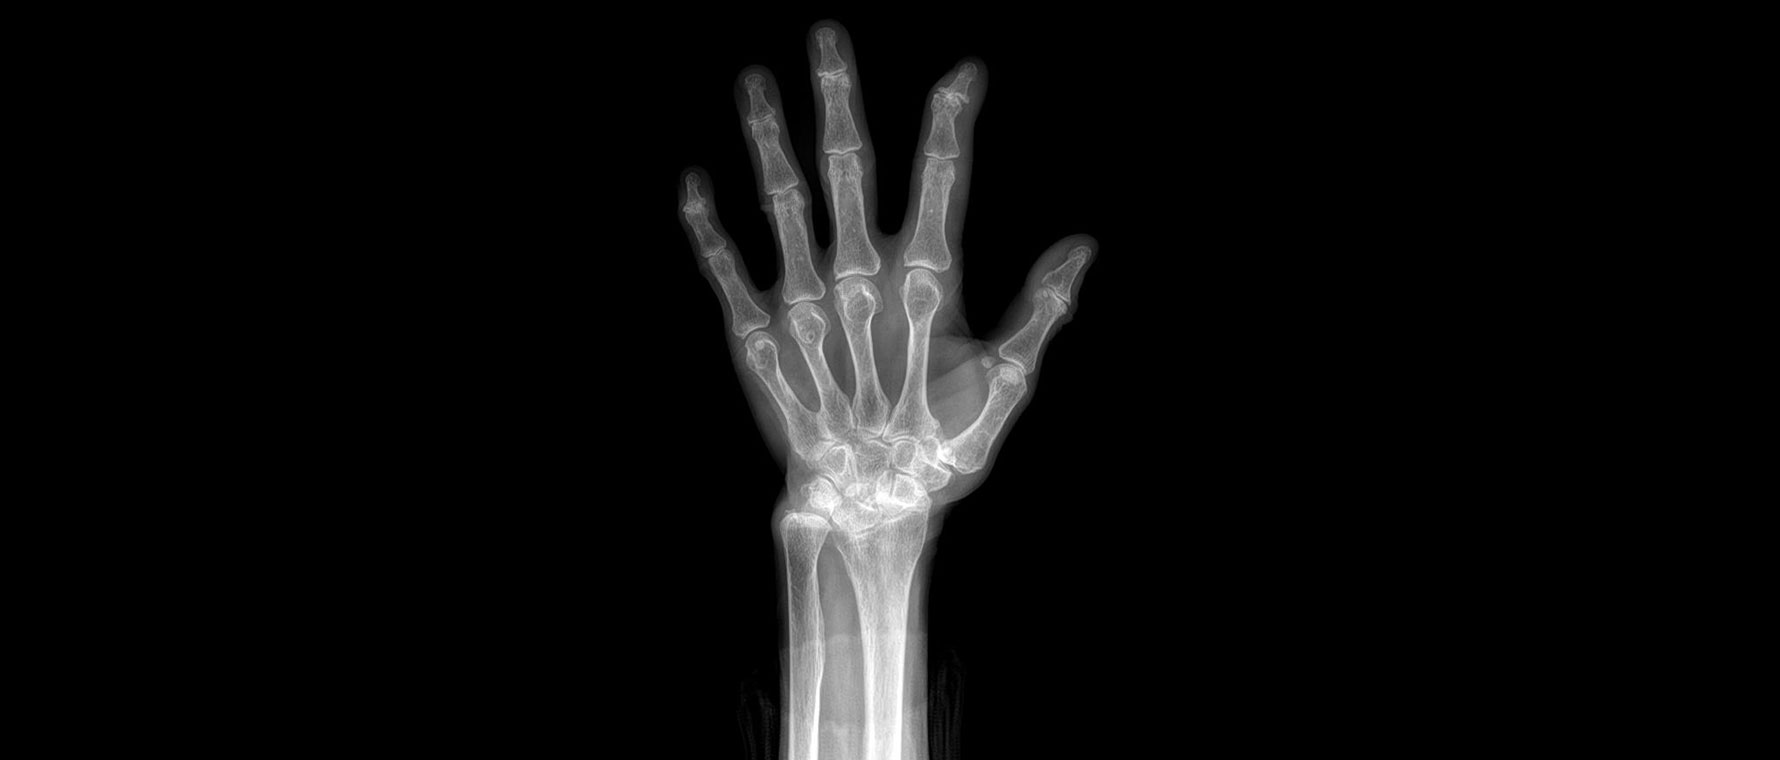

Başparmak Kök Eklem Kireçlenmesi (1.cmc Eklem Artrozu)

Başparmak kök eklem kireçlenmesi, başparmağın bileğe bağlandığı eklemde kıkırdağın aşınmasıyla ortaya çıkar. Özellikle kavrama ve sıkma hareketlerinde ağrıya yol açar. Hastalar kapak açma, anahtar çevirme gibi işlerde zorlanır. Zamanla şekil bozukluğu gelişebilir. Tanı muayene ve röntgen ile konur. Tedavide atel, ilaçlar, egzersiz ve enjeksiyonlar uygulanır. Şikâyetleri ileri düzeyde olan hastalarda cerrahi seçenekler gündeme gelir. Cerrahi artroskopik ya da açık cerrahilerle kireçlenen kemik yüzlerinin tıraşlanması ve başparmak kök eklemini yerinde tutan bağların çevre tendonlarla onarılmasını içerir.